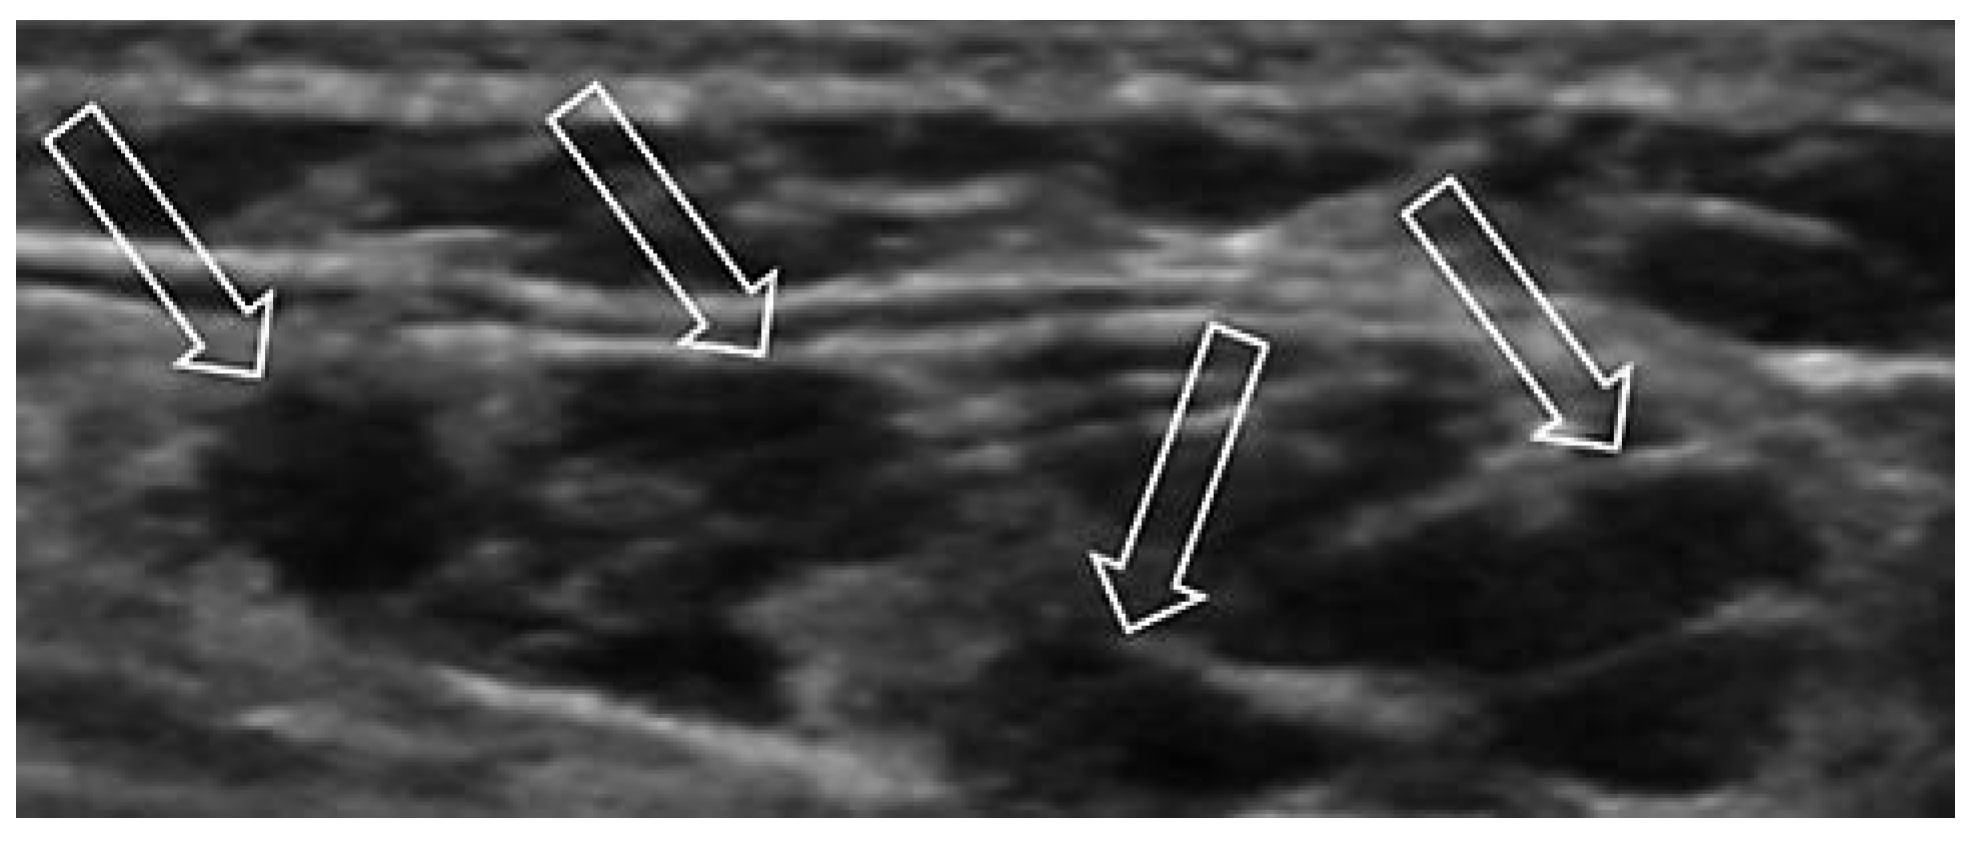

Venöse Malformationen

Lymphatische Malformation